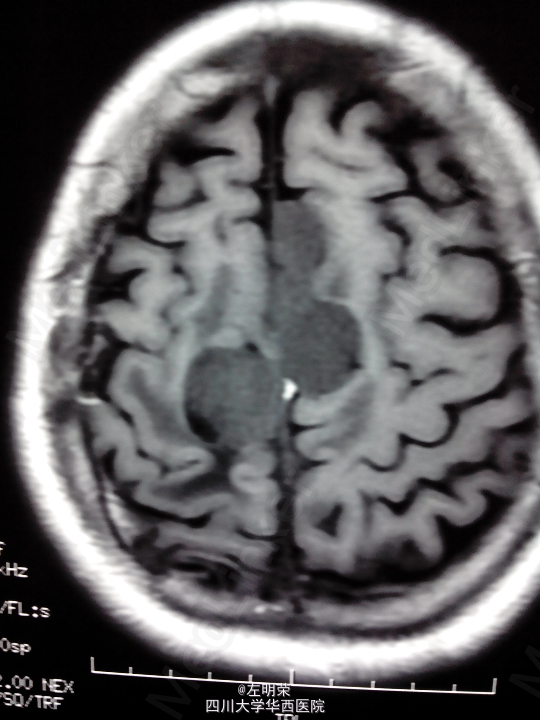

脑膜瘤术后复发(多发脑膜瘤)

左下肢乏力伴间断抽搐半年+, 患者于5年前行左侧额叶脑膜瘤切除术,术后行伽马刀治疗数次,近来出现肢体无力伴抽搐,不规律服用抗癫痫药物,昨日再发抽搐。

1、多发脑膜瘤 2、继发性癫痫